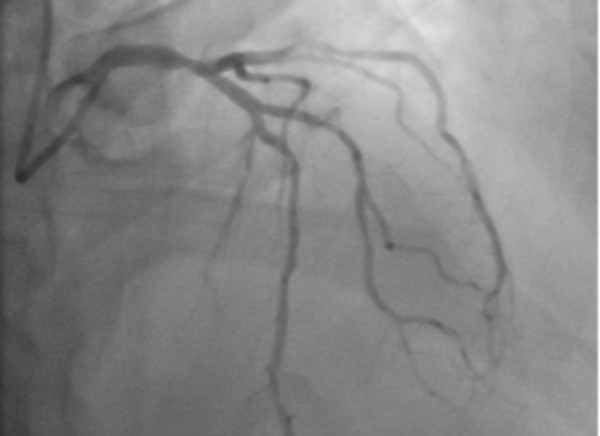

Angiography – a procedure using contrast injected into a blood vessel. It shows blood flow through the arteries and veins of your body to find any blockages, narrowing or aneurisms (bulges in the wall of a blood vessel). Read more about angiography

The image below is an angiogram of the heart blood vessels.

Angiogram of the heart blood vessels

Image credit: Allevia Radiology